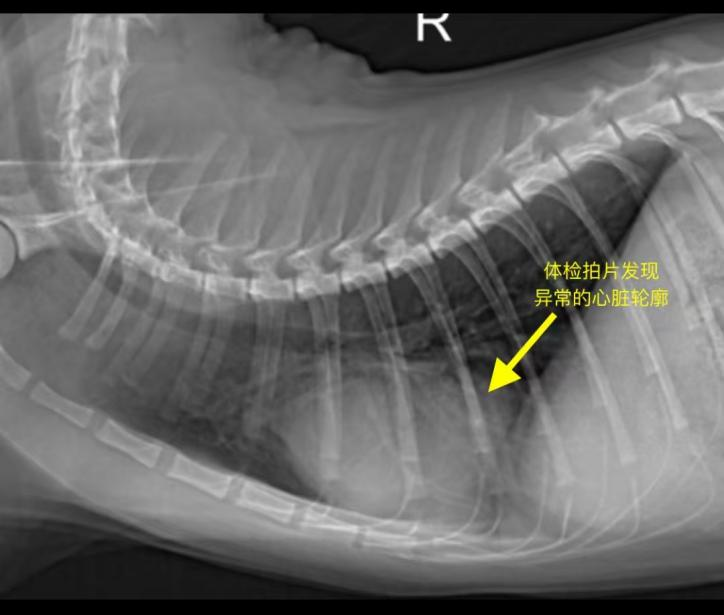

本院在为该猫咪进行体检时,发现其胸部X光片显示心脏轮廓异常。进一步进行心脏超声及腹部超声检查后,确诊为心包横膈疝。该病属于较为罕见的先天性畸形,部分病例可能长期无症状,但若腹腔脏器进入心包腔并产生压迫,可能会影响心脏功能,甚至引发严重的呼吸困难。